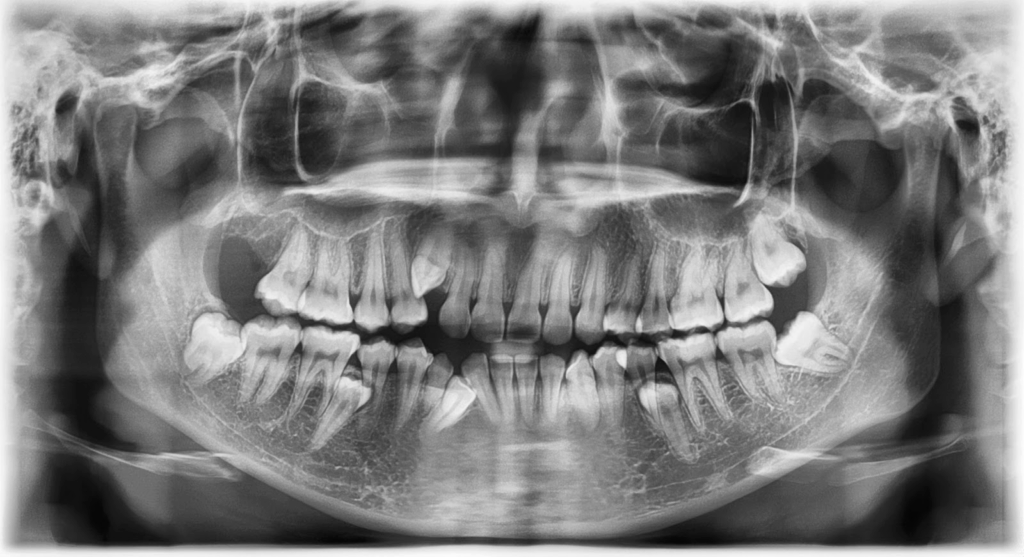

Pacienții cu dentiție uzată prezintă un cumul de probleme care depășesc simpla problemă estetică. Dimensiunea verticală de ocluzie este adesea redusă, ceea ce afectează atât funcționalitatea, cât și aspectul facial. Ghidajele ocluzale devin imprecise, musculatura lucrează ineficient, iar articulațiile temporo-mandibulare sunt supuse unor solicitări anormale. Din punct de vedere parodontal, dinții pot prezenta mobilitate sau poziții patologice.

Factorii cauzali sunt diverși. Bruxismul nocturn produce uzură accelerată și fracturi. Eroziunea determinată de factori alimentari sau medicali duce la pierderea progresivă a smalțului. Igiena agresivă sau obiceiurile vicioase contribuie la abraziune. În timp, dentiția ajunge într-o stare în care pacientul resimte disconfort constant și limitări funcționale evidente.

Pentru medic, aceste cazuri implică o analiză complexă. Este necesară evaluarea articulațiilor, a musculaturii, a parodonțiului și a esteticii faciale. Planul de tratament trebuie să restabilească simultan funcția și armonia, iar orice greșeală de planificare poate compromite stabilitatea pe termen lung.